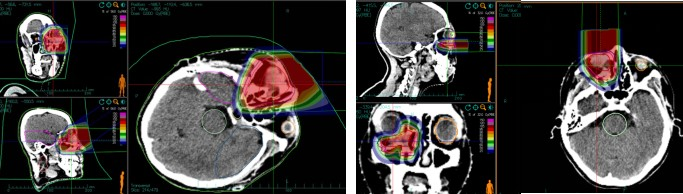

Treatment Plan Implementation:The carbon ion radiotherapy plan involved the patient lying in a supine position, fixed with a vacuum bag and thermoplastic film. CT and MRI images were fused to delineate the target volume. The gross tumor volume (GTV) included the visible right lacrimal sac lesion on enhanced T1-weighted images. The clinical target volume (CTV) encompassed the GTV, right medial rectus muscle, right ethmoid sinus, and right maxillary sinus. Planning target volume 1 (PTV1) was the GTV + 0.3 cm, and PTV2 was the CTV + 0.3 cm. The prescribed dose was 64 Gy (RBE) in 16 fractions for PTV1 and 56 Gy (RBE) in 14 fractions for PTV2. Organs at risk (OAR) dose constraints were as follows: right eye: mean dose ≤ 30 Gy (RBE), right lens: left eye: maximum dose ≤ 9 Gy (RBE), brainstem: maximum dose ≤ 54 Gy (RBE), right optic nerve: 50% isodose line ≤ 56 Gy (RBE), right temporomandibular joint: mean dose ≤ 35 Gy (RBE), optic chiasm: maximum dose ≤ 54 Gy (RBE), left eye: mean dose ≤ 35 Gy (RBE), left lens: maximum dose ≤ 0 Gy (RBE).

Figure 3: First course horizontal field: Prescription dose PTV 56 Gy (RBE)/14 fx; Second course vertical field: Prescription dose PTV = 8 Gy (RBE)/2 f.